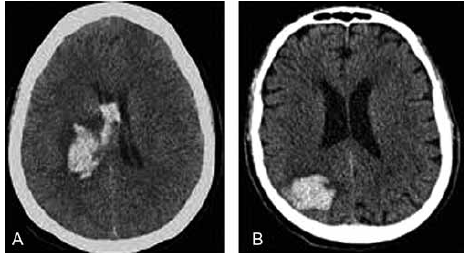

Um paciente de 65 anos é trazido ao pronto-socorro com início súbito de hemiparesia direita e afasia. A tomografia computadorizada (TC) de crânio encontra-se a seguir. O paciente tem histórico de hipertensão arterial sistêmica, mas não está em uso regular da medicação prescrita.

(htpps://sanarmed.com/hemorragia-intraparenquimatosa-casoclinico- e-discussao-radiologica-colunistas/)

Qual abordagem terapêutica inicial é mais apropriada para esse caso?